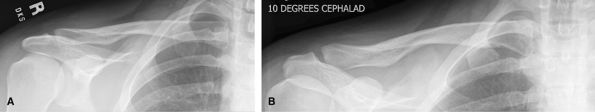

Clavicles

Good for clavicle fractures. Medial clavicle fractures

can be difficult to see. Consider CT for possible medial clavicle

fractures.

Figure 18 (A) AP, 0-degree tube angle. (B) AP, 10-degree cephalad angle.